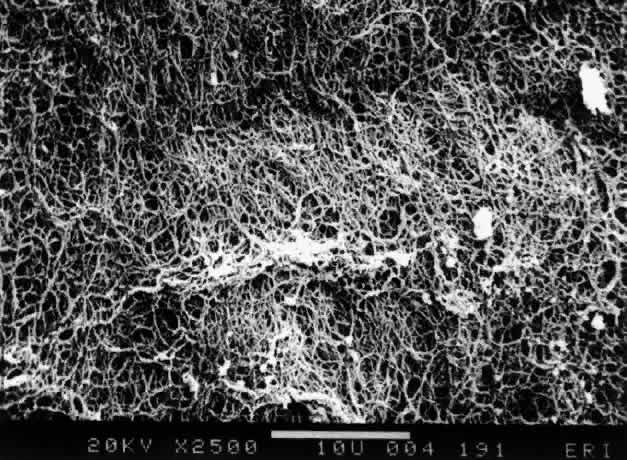

The posterior vitreous cortex is 100-110 μm thick50,60 and, as shown in Figure 12, consists of densely packed collagen fibrils.50,60,152 There is no vitreous cortex over the optic disc (see Figs. 4A AND 13), AND the cortex is thin over the macula due to rarefaction of the collagen fibrils.50 The prepapillary hole in the vitreous cortex can sometimes be visualized clinically when the posterior vitreous is detached from the retina (Fig. 14). If peripapillary glial tissue is torn away during PVD and remains attached to the vitreous cortex about the prepapillary hole it is referred to as Vogt's or Weiss's ring. Vitreous can extrude through the prepapillary hole in the vitreous cortex (see Fig. 4A) but does so to a much lesser extent than through the premacular vitreous cortex (see Figs. 4B AND D and 13). Jaffe153 has described how vitreous can extrude into the retrocortical space created after PVD and has proposed that persistent attachment to the macula (Fig. 15) can produce traction and certain forms of maculopathy.154,155 Although there are no direct connections between the posterior vitreous and the retina, the posterior vitreous cortex is adherent to the internal limiting lamina of the retina, which is actually the basal lamina of retinal Müller cells. The exact nature of the adhesion between the posterior vitreous cortex and the internal limiting lamina is not known but probably results from the presence of various extracellular matrix molecules.91 This concept is supported by studies156,157 in which vitreous cortex separation from the retina was induced using agents that acted on extracellular matrix components that could bind the posterior vitreous cortex to the internal limiting lamina of the retina.

Fig. 12. Ultrastructure of posterior vitreous cortex in humans. Scanning electron microscopy demonstrates the dense packing of collagen fibrils in the vitreous cortex. To some extent this arrangement is exaggerated by the dehydration that occurs during specimen preparation for scanning electron microscopy (bar = 10 [a 5]mm). (Sebag J: The Vitreous--Structure, Function and Pathobiology. New York, Springer-Verlag, 1989)